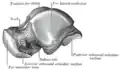

Talus gauche, vue d'en haut.

Talus gauche, vue d'en haut. Talus gauche, vue d'en bas.

Talus gauche, vue d'en bas. Talus gauche, vue médiale.

Talus gauche, vue médiale. Talus gauche, vue latérale.

Talus gauche, vue latérale.